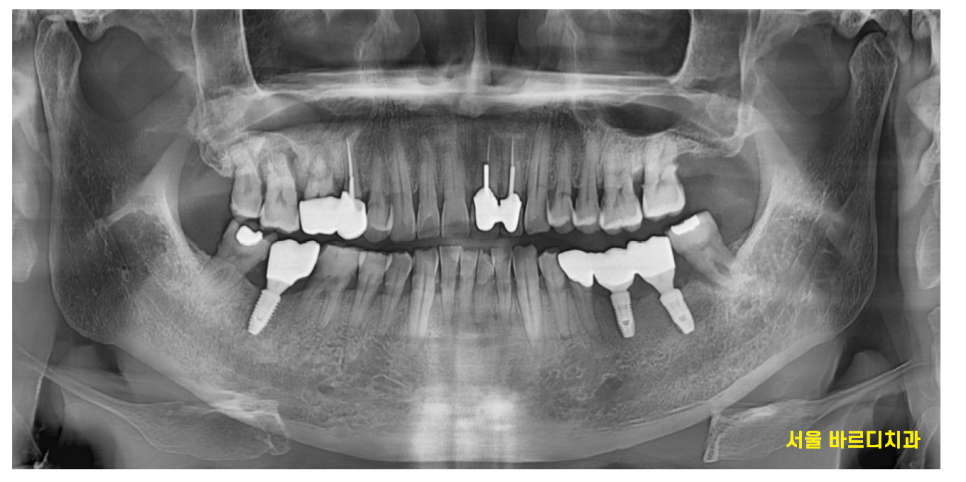

x-ray를 찍어보니

잇몸이 전반적으로 안좋으셨습니다.

그 중에서도 유독~~

눈에 보이는 한 부분이 있네요.

23.07.04

오른쪽 위에 치아가 뿌리 모양이 이상해보였습니다.

역시나 작은 사진을 통하여

검사를 해보니

뼈가 많이 녹았네요.

염증으로 인하여 잇몸 뼈가 녹고

그로 인하여 잇몸이 들뜨니

치아 솟음 느낌을 받으신거죠.